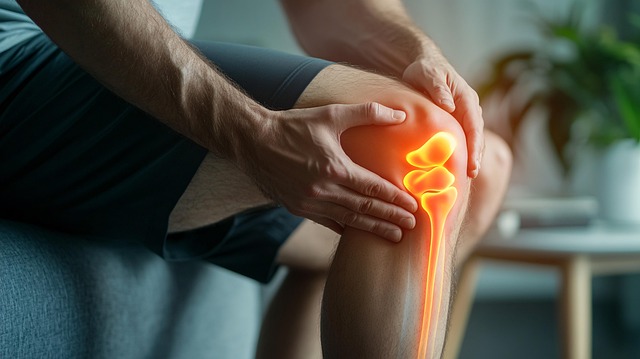

2. 관절과 무릎 통증 완화

복용 후 무릎의 뻣뻣함, 통증이 줄어들었다는 체감 후기가 다수입니다. 특히 아침 기상 직후 관절이 더 부드러워졌다는 경험담이 많습니다. 단순 통증 억제가 아닌, 뼈 자체를 강화함으로써 일상 속 불편을 줄여준다는 점에서 만족도가 높습니다.